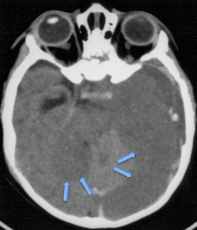

les variations du drainage veineux

il existe chez l’enfant des sinus duraux persistants, de taille variable, mais généralement d’autant plus problématiques que l’enfant est petit.

dans certains cas, un sinus latéral est remplacé par une sinus médian ou paramédical qui ne peut pas être sacrifié. il faut alors trouver une variante de l’abord habituel permettant de mener à bien l’intervention.

sinus occipital paramédian ; l’incision parallèle au sinus, avec extension vers le bas, a malgré tout permis un abord correct du 4ème ventricule.